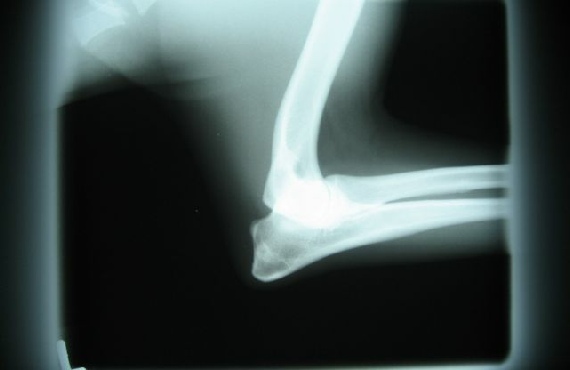

HD / ED RÖNTGENBILDER VON FACE

26.08.08 bekam ich eine Narkose (das fand ich gar nicht toll !!) , aber scheinbar sind diese Röntgenbilder, über meine Hüft- und Ellenbogengelenke, die dann gemacht wurden, ziemlich wichtig.